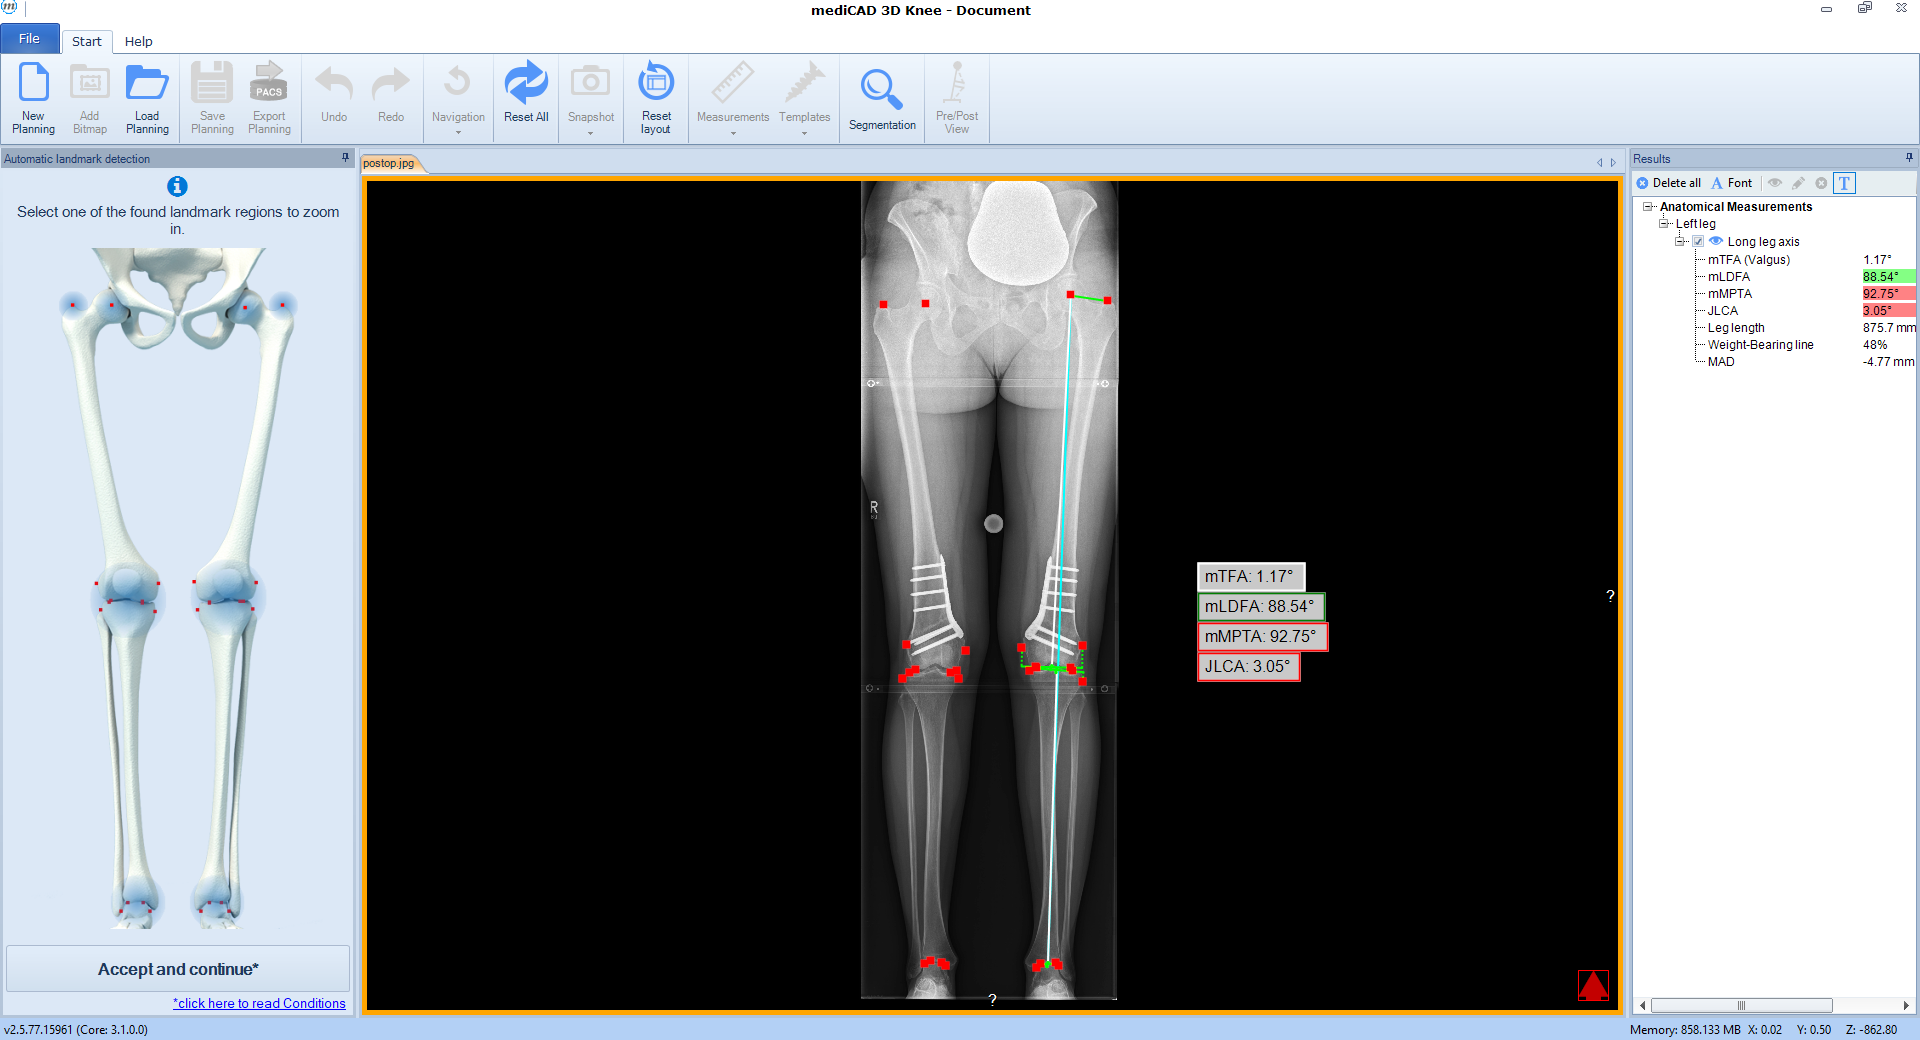

The software automatically detects all necessary landmarks (Fig 1). Based on their position (which can be adjusted manually) the software calculates all essential values (axis, joint lines, and angles) and delivers a detailed report. A traffic light system illustrates normal, intermediate, or pathological values.

Following the deformity analysis, the software automatically recommends a surgical procedure, eg, medial opening wedge high tibia osteotomy, depending on the type of deformity (Fig 2). The user can follow the proposed procedure or choose individual options.

Once the procedure is selected, the software automatically places the cutting line and hinge point for the chosen osteotomy adapted to the individual anatomical condition (Fig 3).

Next, deformity correction is visualized to the preferred new alignment. If a monofocal correction results in pathological joint angles, the implemented algorithm recommends double-level osteotomy and balance the two osteotomies between multiple constraints and normal values such as wedge heights, mechanical medial proximal tibial angle (mMPTA), mechanical lateral distal femoral angle (mLDFA), mechanical tibiofemoral angle (mTFA); (Fig 4).